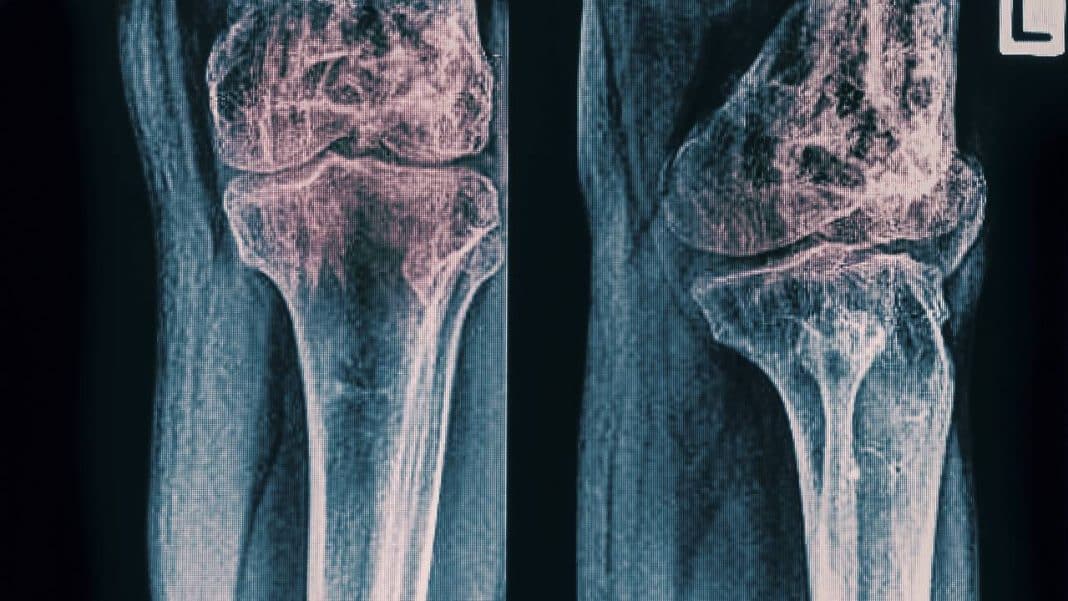

Las moléculas de la mucosidad pueden utilizarse para producir material sintético de injerto óseo y ayudar en la curación de grandes pérdidas óseas. De esta manera, se pueden contribuir a la curación de lesiones graves en los huesos. Esta innovación abre nuevas posibilidades en el campo de la biotecnología médica.

El éxito de la curación de la lesión ósea depende de la integración del nuevo hueso con el hueso huésped. Su posterior aceptación por el sistema inmunológico del cuerpo. Sin una adecuada integración y aceptación, el hueso recién formado no puede recibir la sangre y los nutrientes necesarios para su crecimiento y consolidación.

Esto puede resultar en una curación insuficiente y en una pérdida de función en el hueso afectado.